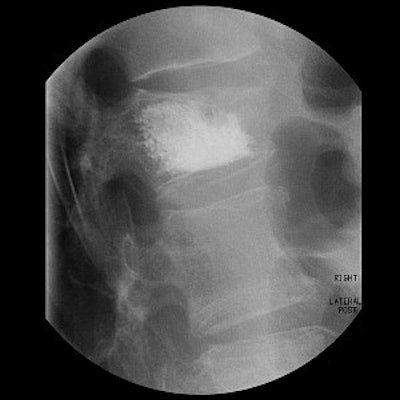

Above, the acrylic bone cement flows into the vertebra, filling the trabecular spaces within the bone. Inset shows a magnified view of the interior of the vertebra with the cement filling in the spaces. Below, the restored vertebra with the hardened cement, stabilizing the vertebral structure and relieving pain. Inset shows magnified view of the interior of the restored vertebra.